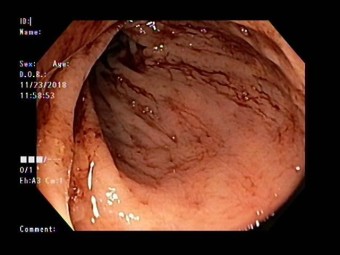

대장내시경은 대장암을 90% 이상 선별하는 방법으로 알려져 있어요. 대장 내시경 검사 시 실제로 암이 발견되면 정밀 검사를 받아야 해요. 먼저 정확한 진단을 받기 위하는 것은 대장내시경 전 식품 유의사항을 정확히 지키는게 중요해요. 식품 유의사항을 잘 지켰다면 병원을 방문하여 검사를 받게 되는데, 검사 시 편한 옷을 갈아입고, 왼쪽 방향으로 옆으로 누운 다음 무릎을 구부린 자세를 취해요. 그다음은 수면 내시경으로 진행한다면 진정제를 투입하면 잠이 들면 항문을 통해 의료 내시경을 삽입하여 검사를 하게 되어요. 비수면의 경우 내시경 삽입 시 강력한 힘이나 말을 하게 되면 삽입이 어려울 수 있기 때문에 긴장을 가능한 한 풀고 진행하게 되어요. 검사 시간은 환자에 따라 조금씩 다르지만 20-30분 정도 소요된다고 해요.